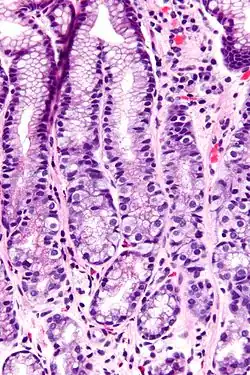

Structure

G cells have a distinctive microscopic appearance that allows one to separate them from other cells in the gastric antrum; their nuclei are centrally located in the cell. They are found in the middle portion of the gastric glands.